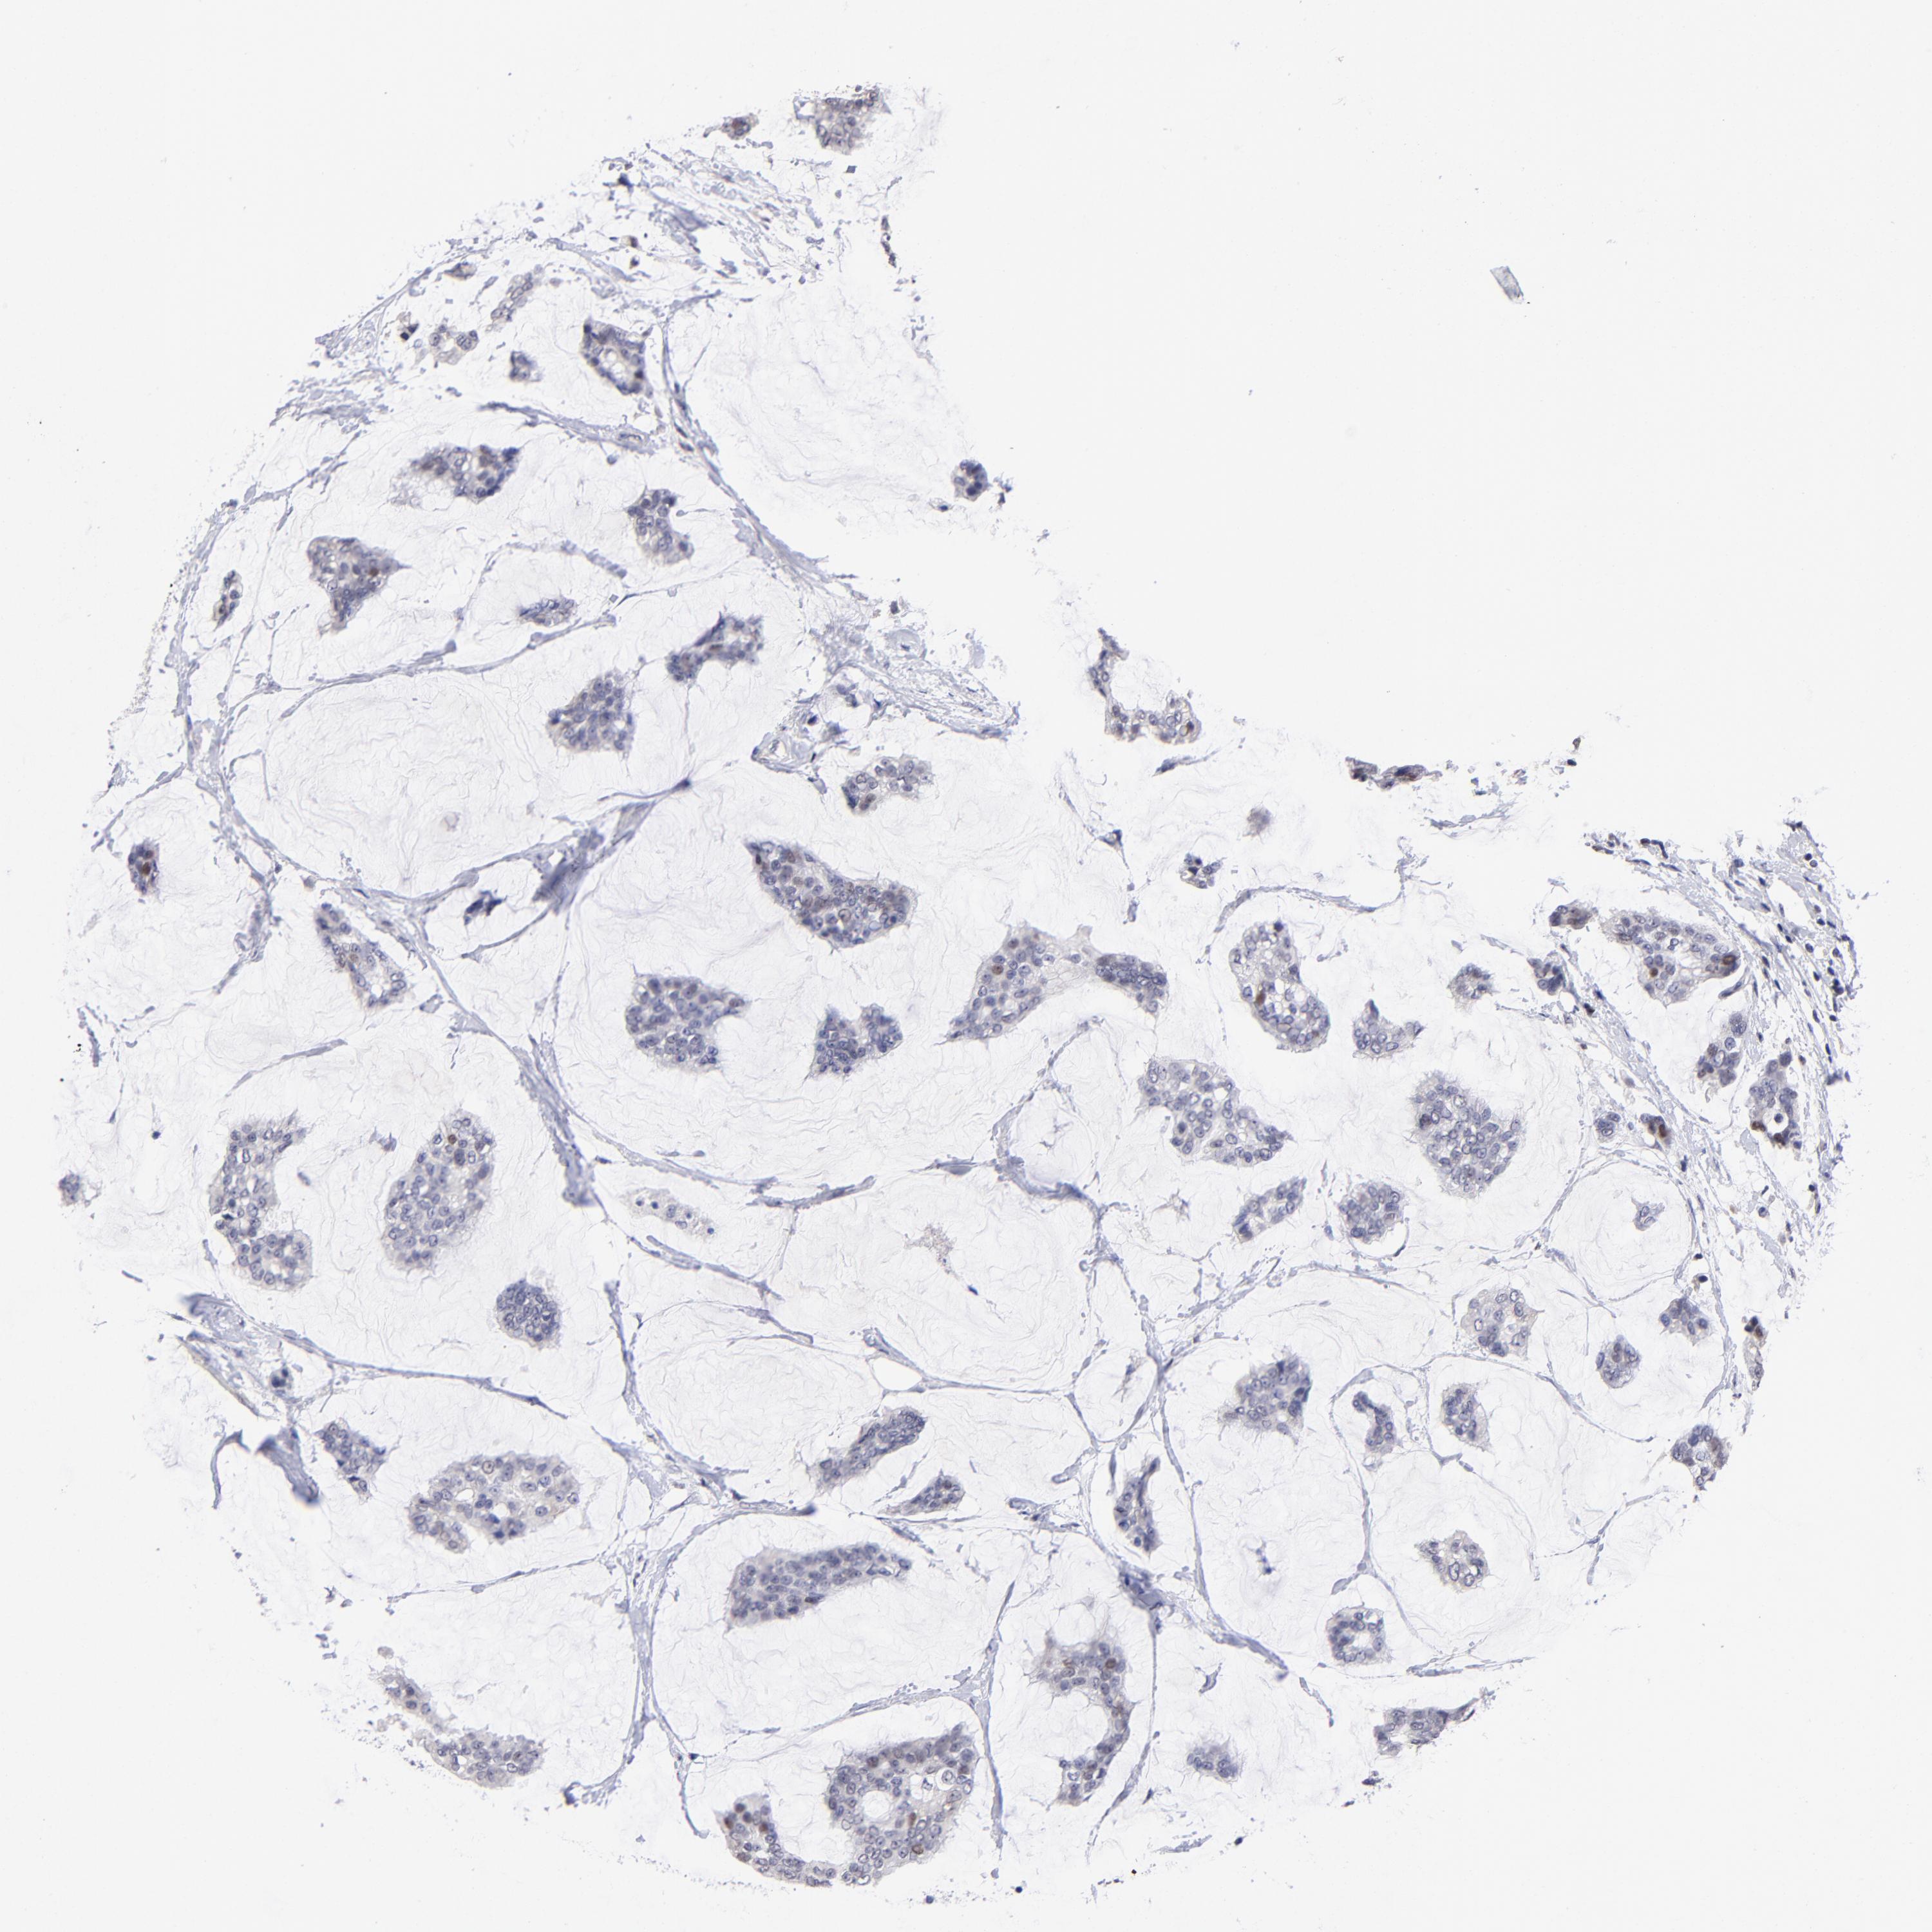

BRCA TCGA BRCA VALIDATION PROTEIN EXPRESSION